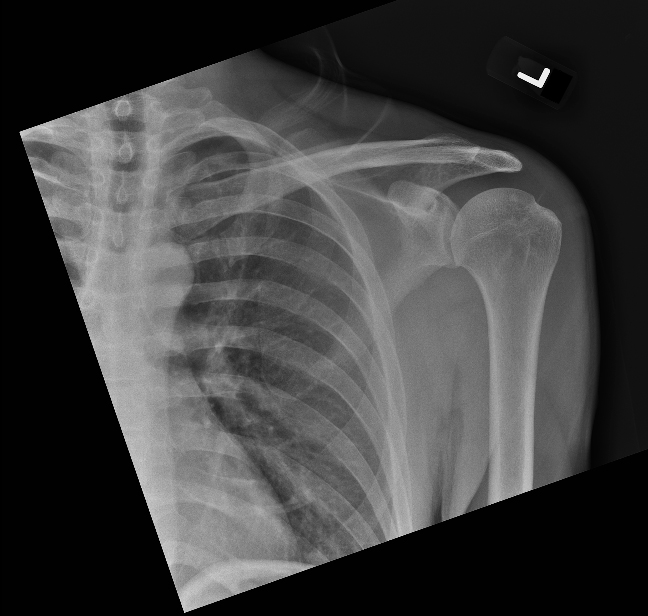

| 13 |

Abnormal dis |

Abnormal Right shoulder posterior dislocation |

Correct |